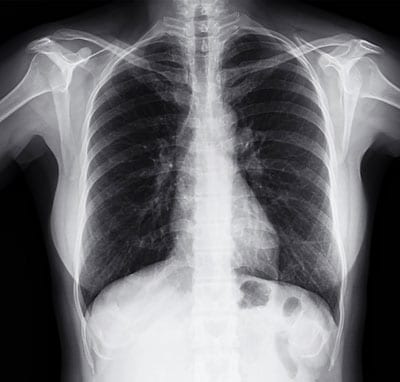

Your doctor has specialized tests to evaluate and diagnose pulmonary hypertension. Common tests often include an EKG, or electrocardiogram, and a heart catheterization of the right side of the heart. Your physician may also order a lung function tests, a CT scan of your chest or an MRI, blood tests, as well as any other tests they deem appropriate to diagnose any underlying condition and develop an appropriate treatment plan.